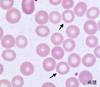

RBCs and platelets

Red blood cells

Ca. 7 µm in diameter. Most numerous type of cell in blood. One microlitre of blood contains ca. 5 million cells. Essential for transport of CO2 and O2 around the body.